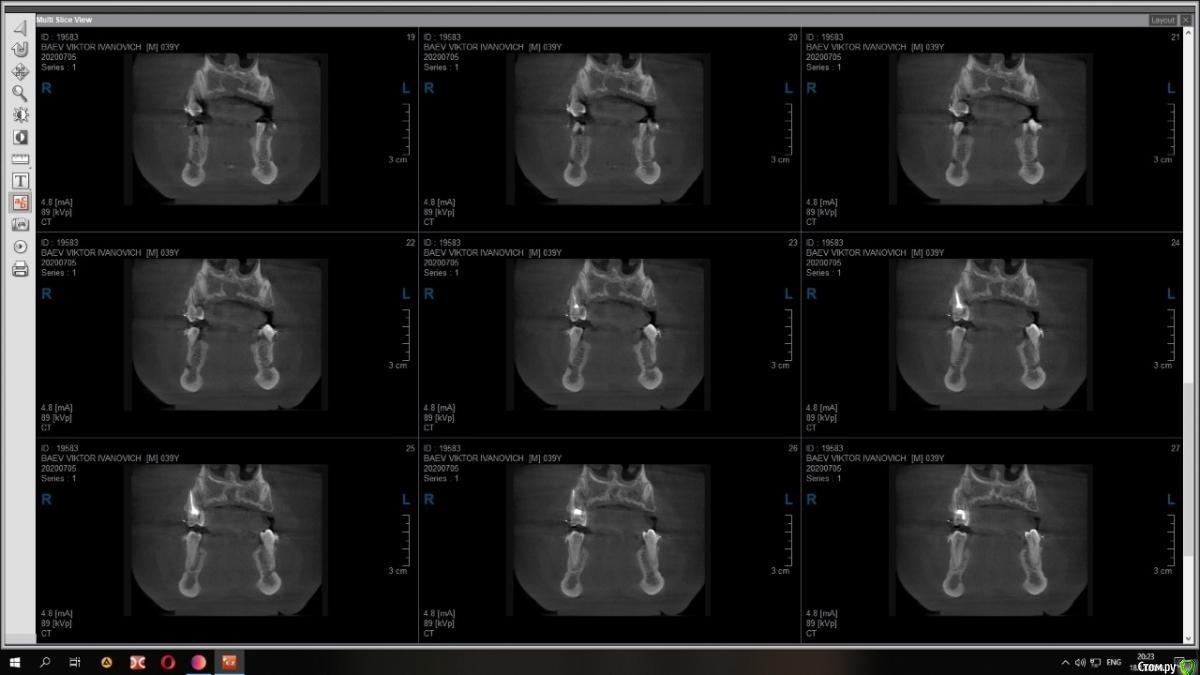

Raystom Опубликовано 15 декабря, 2020 Поделиться Опубликовано 15 декабря, 2020 Случайно на КТ перед имплантацией 36 обнаружили образование. Похоже на кисту резцового канала. Срезы снимка прилагаются.Варианты решения:1. Стационар и ЛОР, т.к. судя по снимку она, на мой взгляд, состоит из 2х частей и есть очень большая вероятность прорастания в носовой ход2. Убирать самостоятельно, но тут возникает очень много вопросов. С нёба доступ самый простой, но потом непонятно как закрыть костный дефект так, чтобы была возможность восстановления кости. При вестибулярном доступе предварительно придется делать эндо 111 с последующей резекцией, но, непонятно, удастся ли его вообще сохранить. Ещё момент, если убрать только обширную часть (нижний компонент), положить резорбируемую мембрану на дно, а аугментат через 2 месяца, дабы не пророс. При этом верхний компонент убрать с помощью ЛОР-эндоскопии.И организационный вопрос, как будет лучше, как и планировалось провести имплантацию 36, дать человеку отдохнуть на новогодних праздниках, а после уже лечение по поводу кисты Ссылка на комментарий

Raystom Опубликовано 21 декабря, 2020 Автор Поделиться Опубликовано 21 декабря, 2020 Киста то малюсенькая. Вскрыть и почистить. Нёбно конечно же. Можно положить мембрану, в полость ничего не класть. В нос я бы вообще пока не лез. меня смущает 3 момента, первый это то, что она прилетит рядом с апикальной частью 11, второй это то, что мне показалось она состоит из 2х частей и третье, это то, что она около 1см в диаметре (просто пока она не выросла и натворила дел, с ней можно что-то сделать) плюс ко всему стоят брекеты и мне кажется это может ускорить процесс роста кисты Ссылка на комментарий